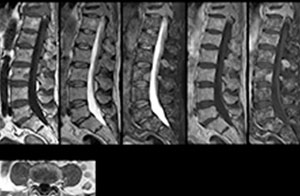

“We use mDIXON TSE extensively in our spine imaging in the emergency room,” says Dr. Karis. “It’s particularly nice in that it is very robust with regard to susceptibility type of problems that would come up with traditional spectral fat-saturated images; these problems are essentially eliminated with the mDIXON technique. In our ED environment it’s really nice to have the fat-free imaging that goes along with the mDIXON technique.

“For the thoracic and cervical spine routine non-contrast exam, for example, we perform one mDIXON T2 TSE sequence, which provides us with two outputs: the fat-and-water-together T2-weighted images, as well as the water-only sagittal T2-weighted images. And then we also perform an axial gradient echo exam.”